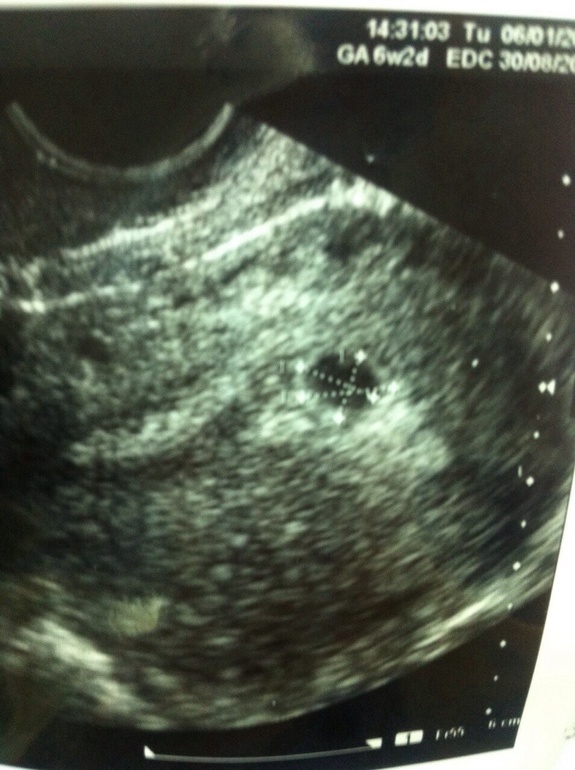

УЗИ, КТГ, доплерТолько что пришла домой с узи:) масенькое яичко 8 мм сидит в домике, гораздо меньше, чем я ожидала:) дело в том, что м были 23 ноября, а числа 10-го декабря мне показалось, что левый яичник рванул. На том и порешила. А еще через несколько дней, числа 15-го начал болеть правый. Я подумала, что это вторая О, после отмены ок не так много времени прошло. И вот, 28-го числа сделала тест, думая, что задержка уже. Ну а там полосочки:) а сегодня выяснилось, что ЖТ в правом яичнике, а левый просто в шутку тянуло, он не овулировал. Поэтому тест я сделала еще до задержки:) и сейчас нам 5 неделек:) сдала хгч и прогик

Растите здоровенькими! У меня примерно срок меньше вашего на недельку, и мы вчера на узи были 2.6 мм всего.